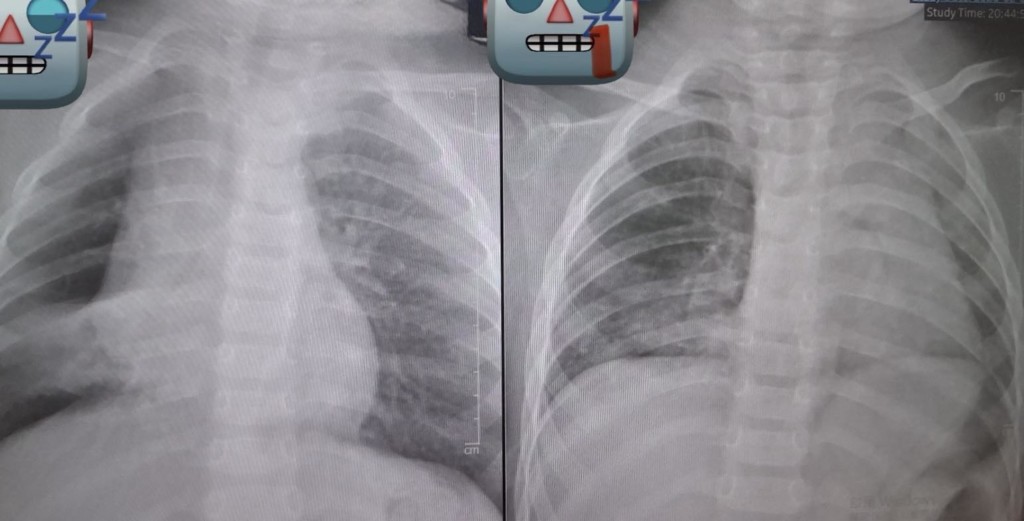

廖穗綾在貼文開頭直呼「到底為什麼還要餵小小孩吃整顆花生?」病房來了一個一歲多的孩子,3、4天前阿嬤餵了花生,之後開始咳嗽、出現喘鳴聲,剛來時症狀並不明顯,但隔天追蹤X光,竟發現肺部開始塌陷,這不是小事。